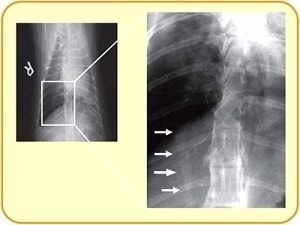

検査法③ レントゲン検査

肺や気管支の見え方、特に肺動脈の太さがヒントになります。

咳をしているネコちゃんは、レントゲンを撮ってみるといろいろ見えてくるかもしれませんね。